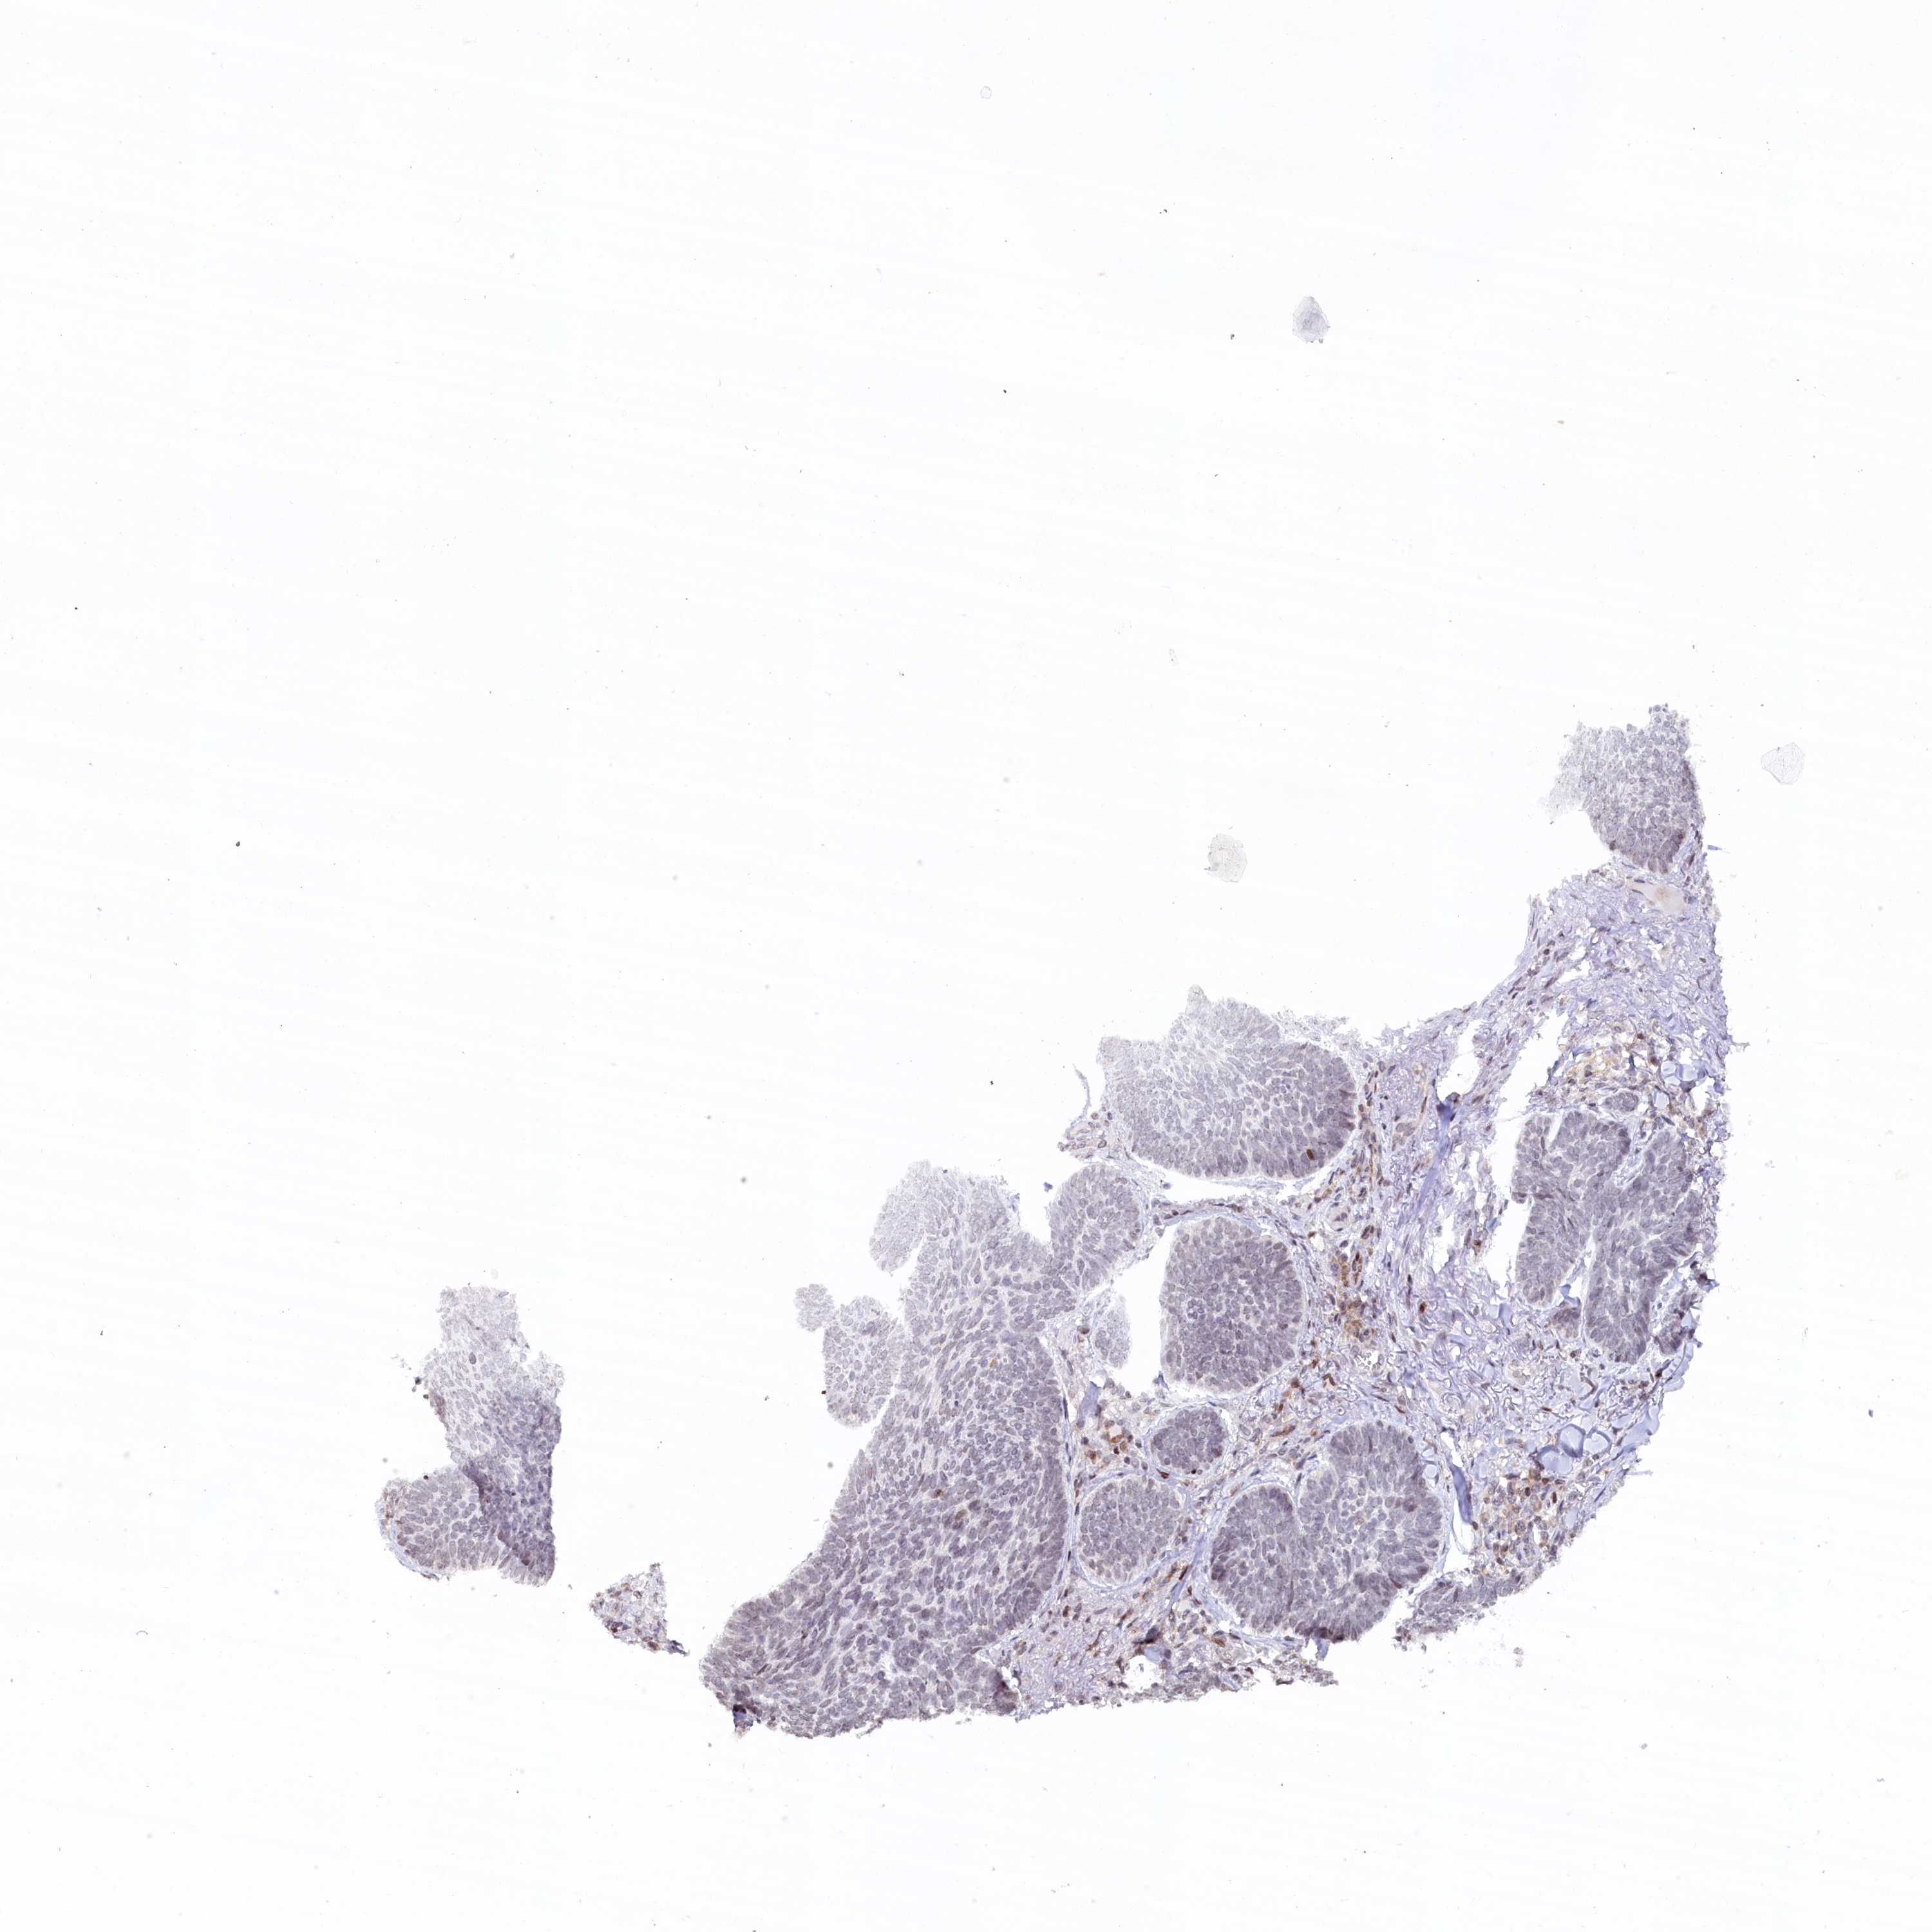

SKIN CANCER - Protein expressioni

A mouse-over function shows sample information and annotation data. Click on an image to view it in a full screen mode. Samples can be filtered based on level of antibody staining by selecting one or several of the following categories: high, medium, low and not detected. The assay and annotation is described here.

Antibody staining in the annotated cell types in the current human tissue is reported as not detected, low, medium, or high, based on conventional immunohistochemistry profiling in selected tissues. This score is based on the combination of the staining intensity and fraction of stained cells.

Each image is clickable and will lead to virtual microscopy that enables deeper exploration of all samples and also displays staining intensity scores, fraction scores and subcellular localization as well as patient and tissue information for each sample.

Antibody CAB025336

Squamous cell carcinoma, metastatic, NOS

Squamous cell carcinoma, NOS